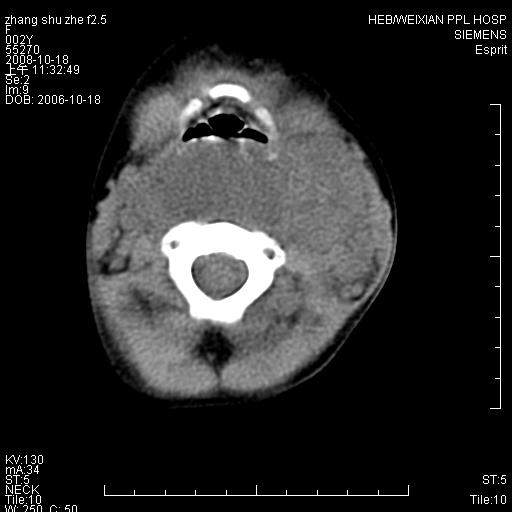

以下是引用dyqct在2009-2-10 21:04:00的发言:[br]年龄?性别?有发烧吗?[br]鼻咽部、口咽部、喉咽部及颈椎前间隙广泛肿厚,明显占位效应并致相应组织变形。ct值22-28hu。[br]考虑:1、颈前脓肿可能性大;[br] 2、建议增强或治疗后复查。

以下是引用jiangjing在2009-2-11 11:37:00的发言:[br]急性病程,鼻咽部、口咽部、喉咽部及颈椎前间隙广泛肿厚,明显占位效应并致相应组织变形.考虑颈部感染性病变(脓肿?);建议行进一步检查。